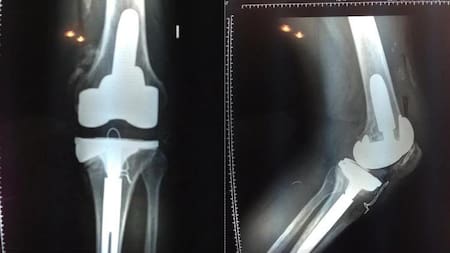

Radiografías practicadas a Ricardo Fort.

En abril de ese año fue operado de esa maldita rodilla: "Fue doloroso, la verdad. Gracias a los calmantes puedo aguantar el dolor y mañana empezaremos con la kinesiología para empezar a mover la pierna y caminar de a poco con muletas", contaría Fort.

La última operación a la que se sometió fue en septiembre: le implantaron 16 tornillos de titanio en la columna, más dos varillas para apuntalarla, y anillos de metal para separar las vértebras y evitar el desgaste de los discos. Aquella cirugía llevó nueve horas, y aunque todo salió bien los problemas no tardaron en llegar luego de que su organismo rechazara los cuerpos extraños, ocasionándole aún más problemas.